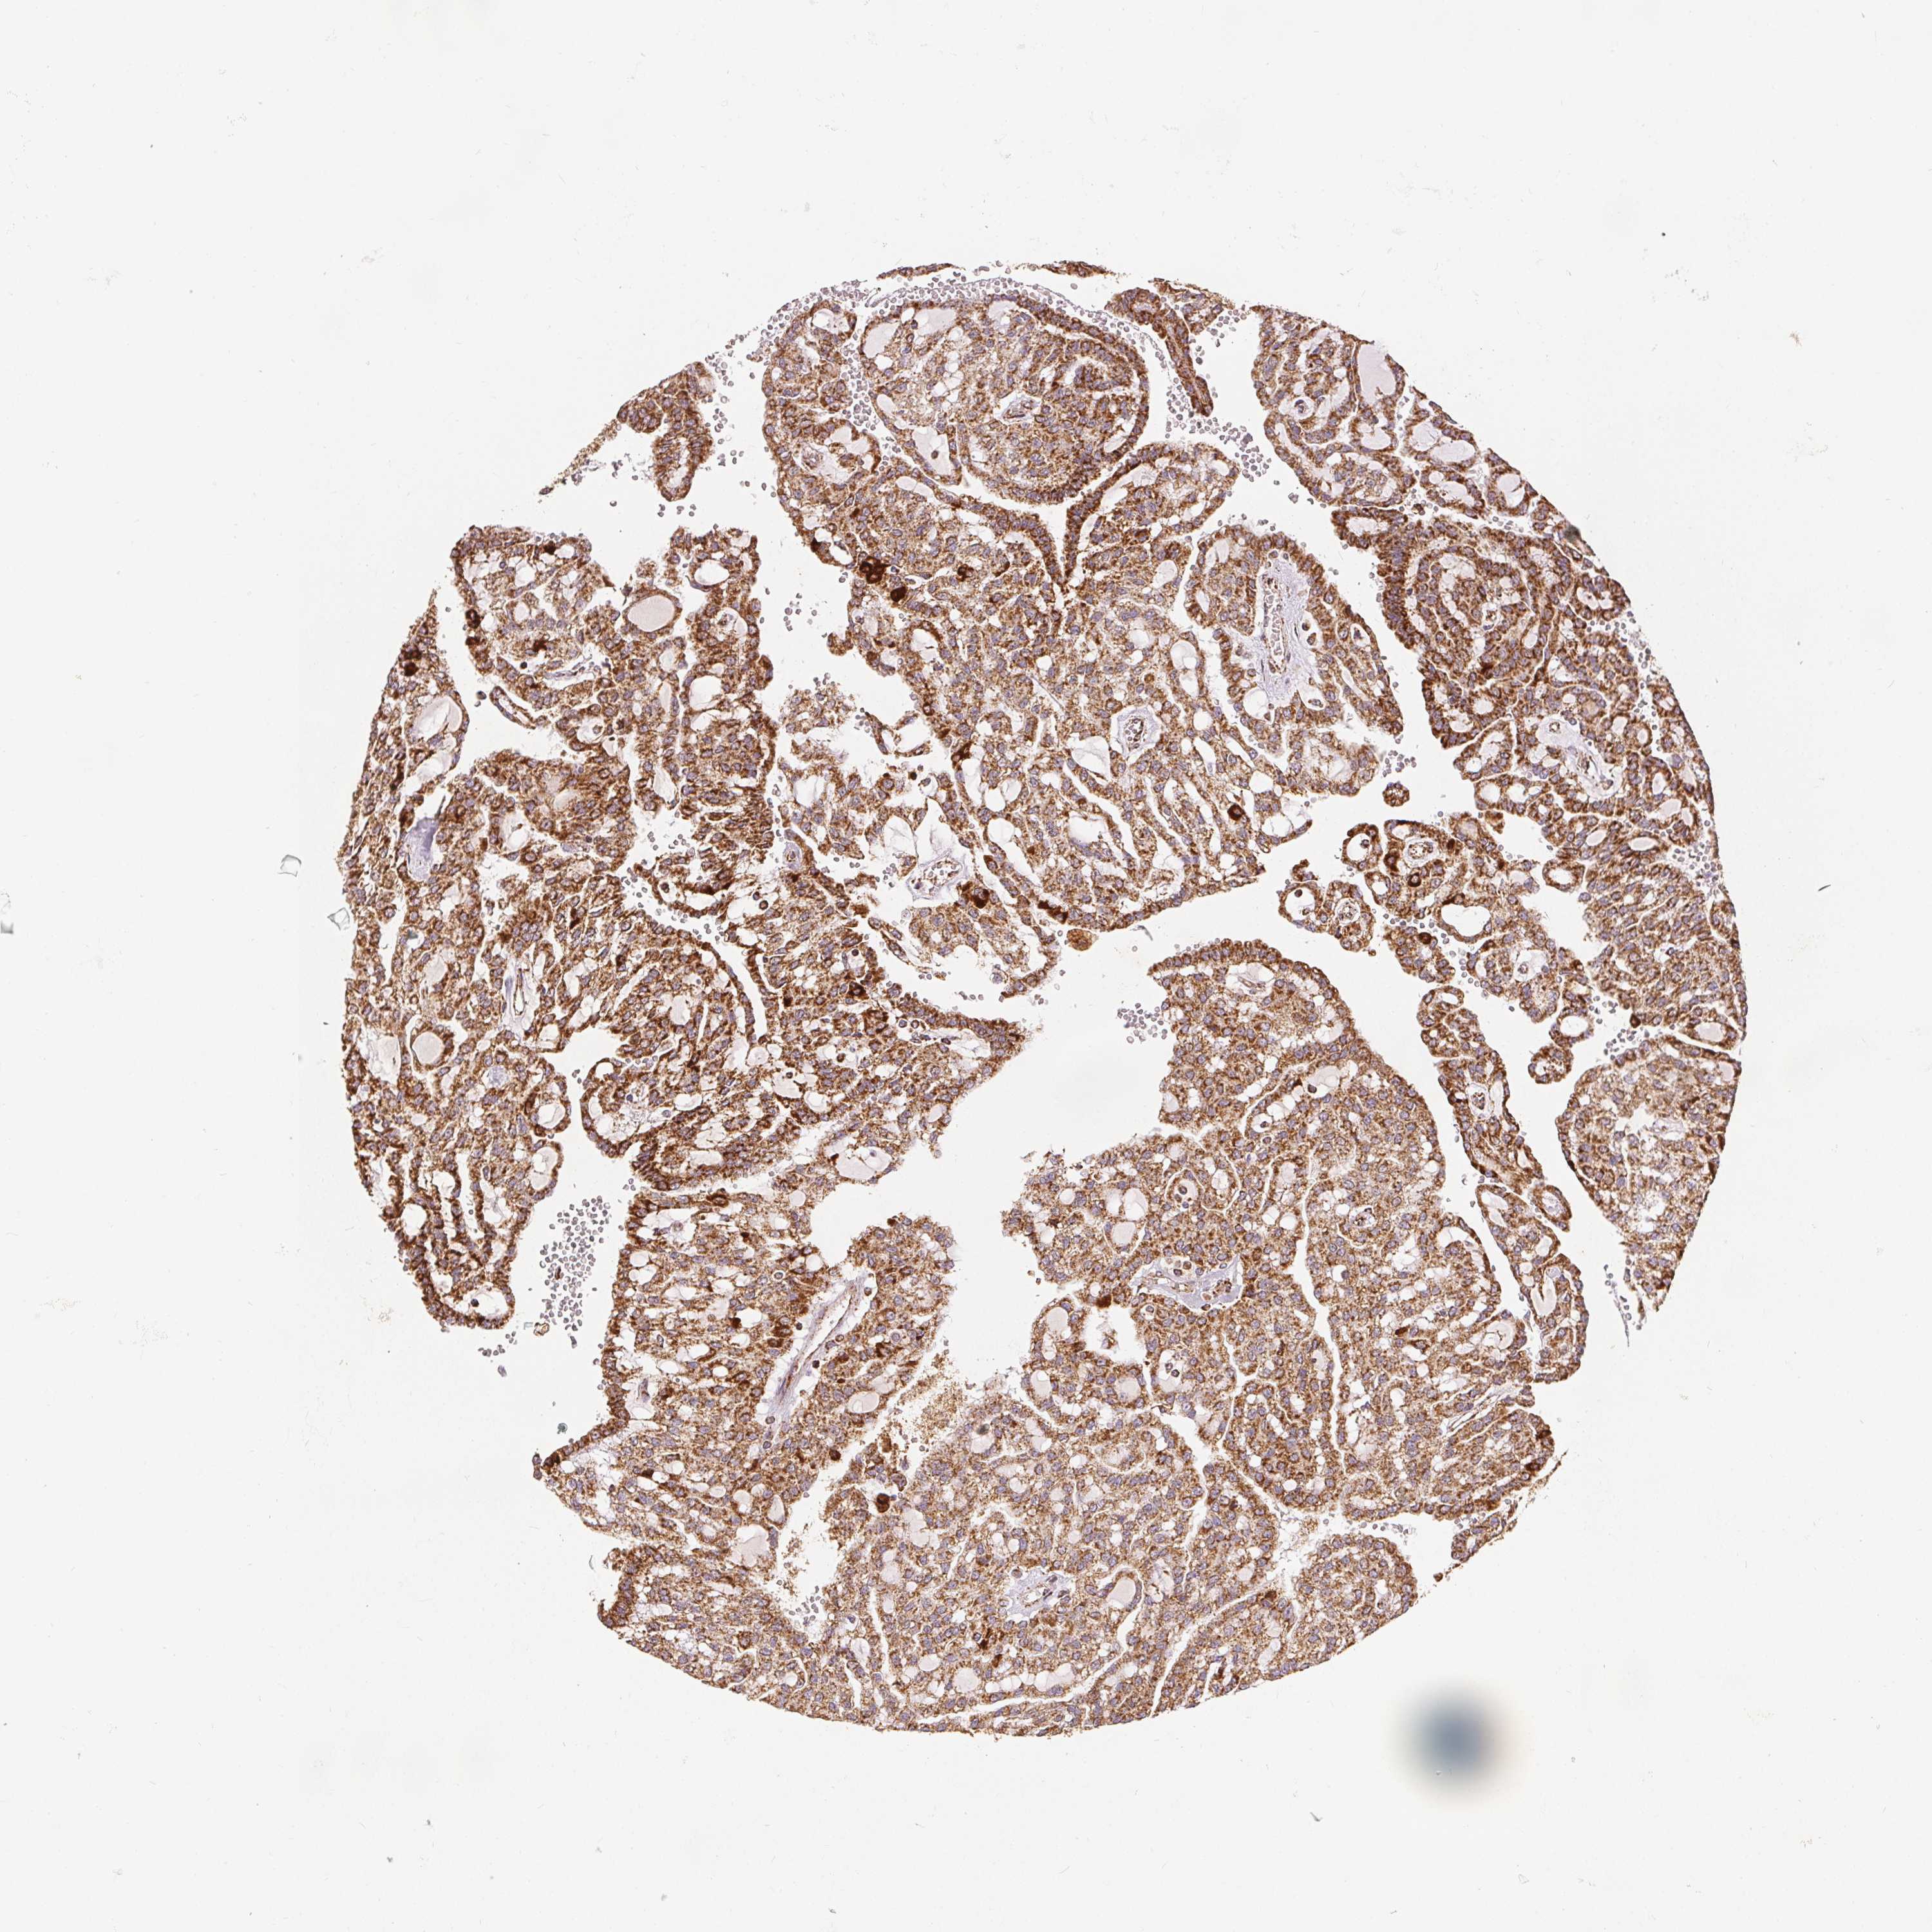

KIDNEY RENAL PAPILLARY CELL CARCINOMA (TCGA) - Interactive survival scatter ploti

The Survival Scatter plot shows the clinical status (i.e. dead or alive) for all individuals in the patient cohort, based on the same data that underlies the corresponding Kaplan-Meier plots. Patients that are alive at last time for follow-up are shown in blue and patients who have died during the study are shown in red.

The x-axis shows the expression levels (FPKM) of the investigated gene in the tumor tissue at the time of diagnosis. The y-axis shows the follow-up time after diagnosis (years). Both axes are complimented with kernel density curves demonstrating the data density over the axes. The top density plot shows the expression levels (FPKM) distribution among dead (red) and alive patients (blue). The right density plot shows the data density of the survived years of dead patients with high and low expression levels respectively, stratified using the cutoff indicated by the vertical dashed line through the Survival Scatter plot. This cutoff is automatically defined based on the FPKM cutoff that minimizes the p-score. The cutoff can be changed by dragging the vertical line or by entering a cutoff value in the square labeled "Current cut-off".

Under the Survival Scatter plot the p-score landscape (black curve; left axis) is shown together with dead median separation (red curve; right axis). Dead median separation is the difference in median mRNA expression between patients who have died with high and low expression, respectively. It is calculated as follows: median FPKM expression of dead patients with high expression - median FPKM expression of dead patients with low expression. This is intended to aid the user in visually exploring custom cutoffs and the associated p-scores and dead median separation.

Individual patient data is displayed and can be filtered by clicking on one or more of the category buttons on the top of the page. Categories describing expression level and patient information include: high, low, alive, dead, female, male and tumor stages. The scale of the x-axis can be toggled between linear and log-scale by clicking on the "x log" button. Mouse-over function shows TCGA ID, patient information and mRNA expression (FPKM) for each patient.

& Survival analysisi

Kaplan-Meier plots summarize results from analysis of correlation between mRNA expression level and patient survival. Patients were divided based on level of expression into one of the two groups "low" (under cut off) or "high" (over cut off). X-axis shows time for survival (years) and y-axis shows the probability of survival, where 1.0 corresponds to 100 percent.